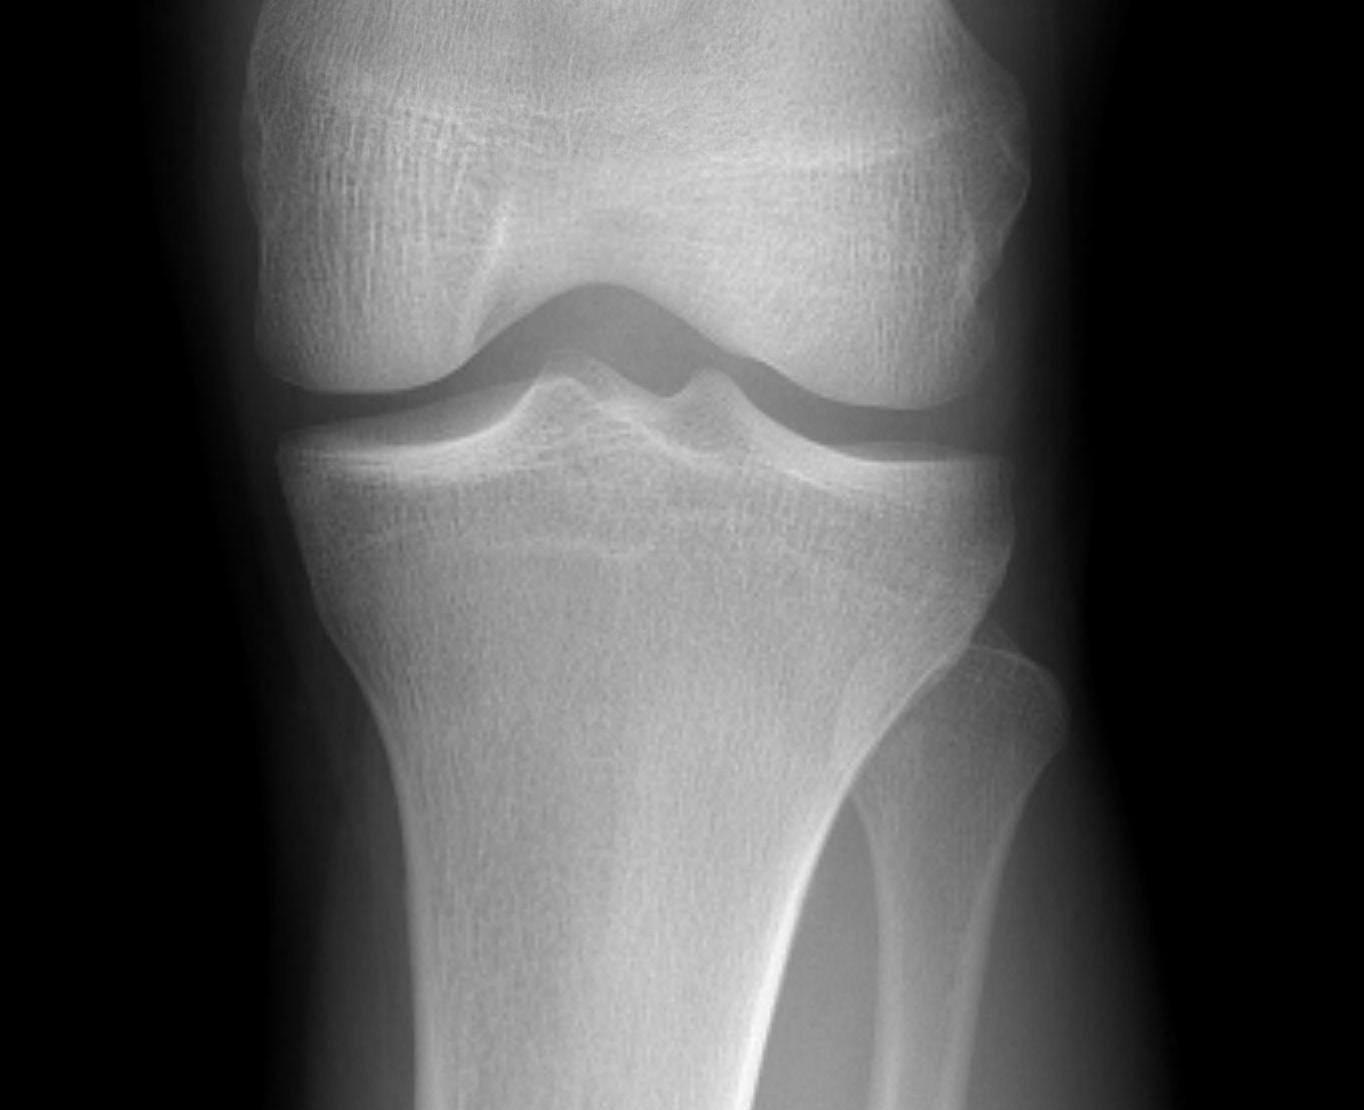

I. Lateral Spilt

- seen in young patient

- lateral meniscus can be incarcerated in fracture